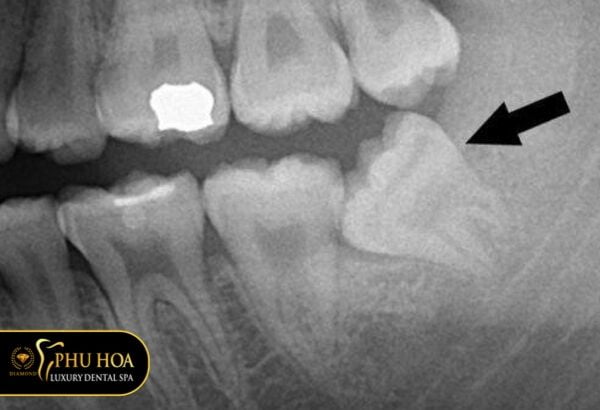

Hình ảnh răng khôn mọc lệch kết hợp ngầm

Nhìn vào tấm hình này ta có thể thấy chiếc răng khi không thể mọc hoàn thiện lên trên phía lợi. Chúng có thể mọc kẹt, mọc ngầm lại và nghiêng sang phía răng khác.

Những răng này có thể gây đau nhức thường xuyên cho người bệnh và nguy cơ sâu răng bên cạnh là rất cao. Nếu phát hiện răng bị mọc lệch kết hợp ngầm, bạn nên xử lý sớm chiếc răng này nhé.